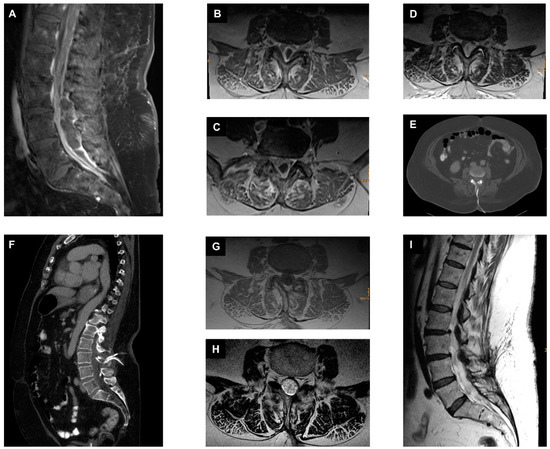

2.3.1. First Case with Isolated Spinal Epidural Empyema

2.3.2. Second Case with Spondylodiscitis and Epidural Empyema